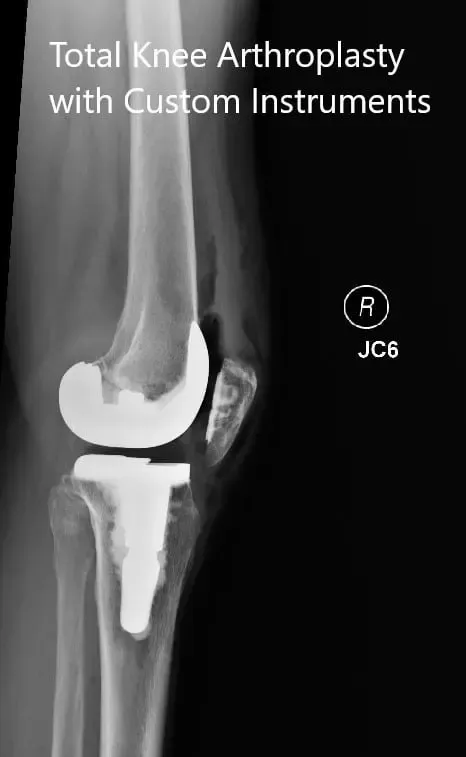

IMPLANTES UTILIZADOS: Fémur estabilizado posterior, talla 3, con una tibia Persona de 5 grados con tallo, tallo C, con inserto de polietileno estabilizado posterior de 10 mm con extensión del tallo de 14 mm de diámetro y rótula cementada de 29 m.

Radiografías postoperatorias que muestran las vistas anteroposterior y lateral de la rodilla derecha.